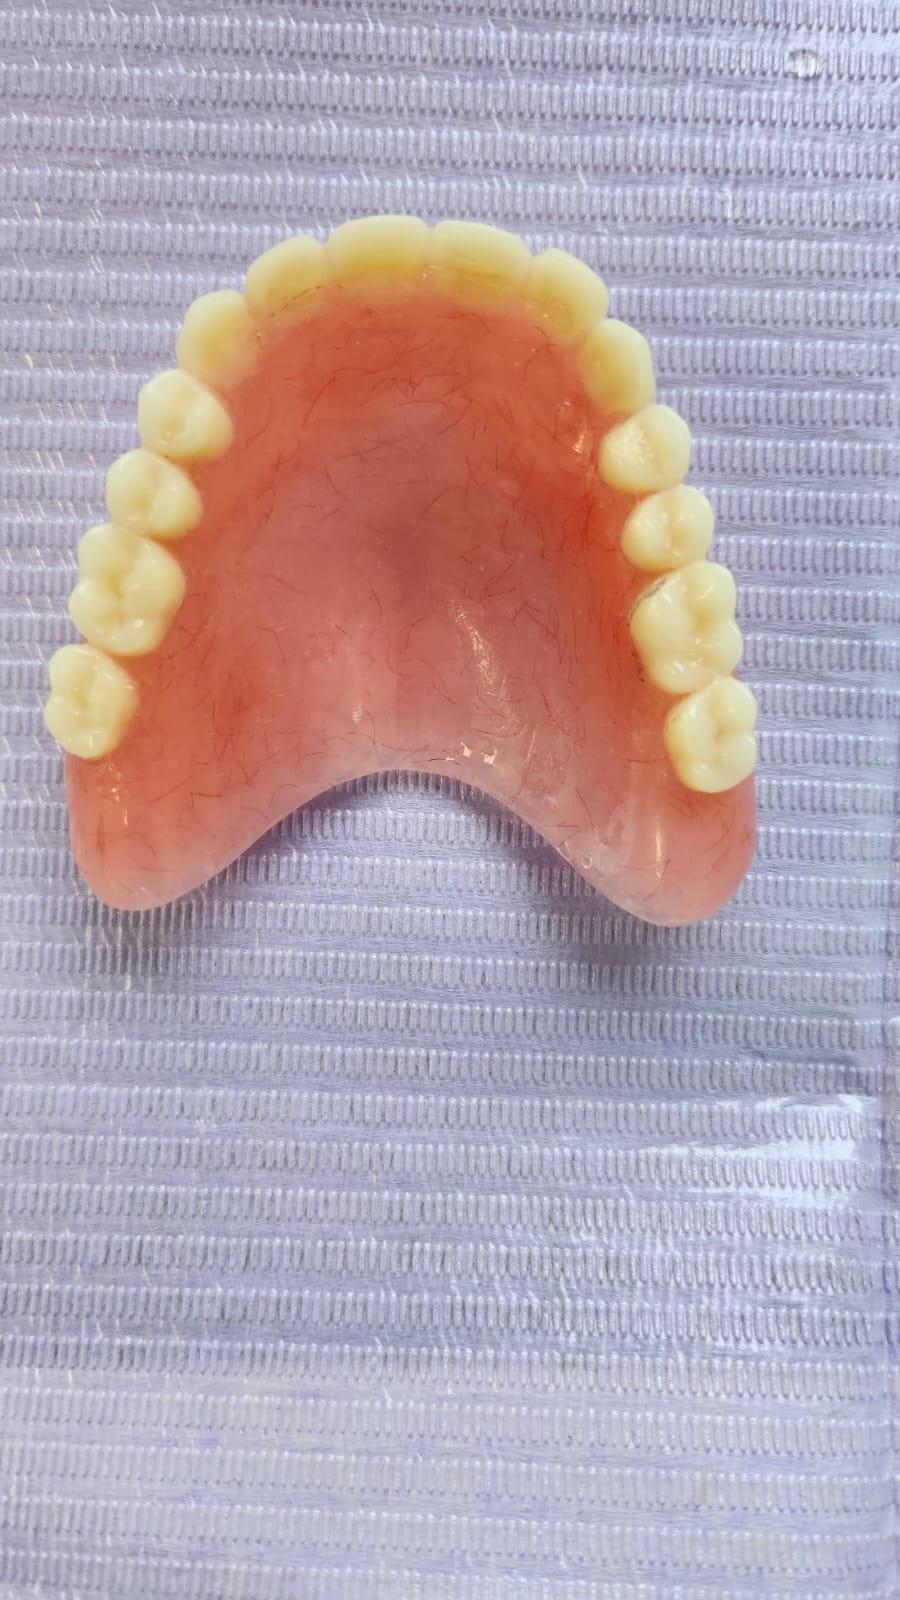

Clinica LUY ESTHETIC ART dispune de ultimele tehnologii in domeniul stomatologic si ofera solutia tratamentelor endodontice, pentru a incerca sa salveze un dinte care a fost distrus in proportii mari. Specialistii nostrii efectueaza acest tratament in mod corespunzator, pentru a evita aparitia altor complicatii ce implica interventii mai complexe: rezectia apicala sau riscul de a pierde dintele.

La Clinica LUY ESTHETIC ART tratamentul endodontic poate fi efectuat pe durata mai multor sedinte, doar cand chisturile dezvoltate sunt medii. Tratamentul nu este dureros deoarece se realizeaza sub anestezie. Pe langa talent, cunostinte medicale, dar si meticulozitate, acest tratament, presupune folosirea unei aparaturi performante: